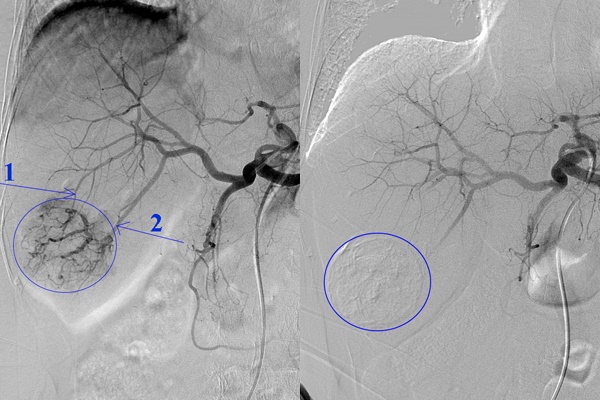

Hình ảnh trước khi can thiệp (ảnh trái) và sau khi nút mạch khối u

Để thực hiện, bác sĩ đặt ống thông từ động mạch đùi luồn vào các nhánh động mạch nuôi khối u, bơm dung dịch Lipiodol và hoá chất, gây tắc các mạch máu nuôi khối u.

Toàn bộ quá trình này mất khoảng 2-3 giờ, được thực hiện trong phòng chụp mạch nên bác sĩ sẽ nhìn rõ các nhánh mạch máu đi vào khối u để can thiệp chính xác.

Phương pháp này sẽ khiến khối u gan bị tiêu diệt bởi 2 cơ chế: Do tác động trực tiếp của hóa chất và do thiếu máu nuôi dưỡng, từ đó giảm kích cỡ, giúp người bệnh cải thiện sức khoẻ.

Sau khi khối u thu nhỏ, bệnh nhân có thể được thực hiện đốt sóng cao tần, sóng viba để diệt khối u.